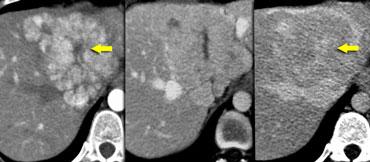

Trước tiên hãy quan sát các hình ảnh bên trái.

Chúng ta thấy nhiều tổn thương giảm tỷ trọng.

Chúng ta không thể chẩn đoán chắc chắn các tổn thương này là:

- Nang: tỷ trọng nước, bờ rõ nét

- U máu (hemangioma): ngấm thuốc ngoại vi dạng nốt tiến triển chậm với tỷ trọng tương đương động mạch

- Tổn thương ác tính: không đồng nhất, bờ không đều, ngấm thuốc ngoại vi thấp hơn tỷ trọng động mạch

Đối với loại tổn thương này, do kích thước quá nhỏ và đặc điểm hình ảnh không điển hình nên không thể phân loại một cách chắc chắn, thuật ngữ TSTC (too small to characterize – quá nhỏ để phân loại) đã được đặt ra.